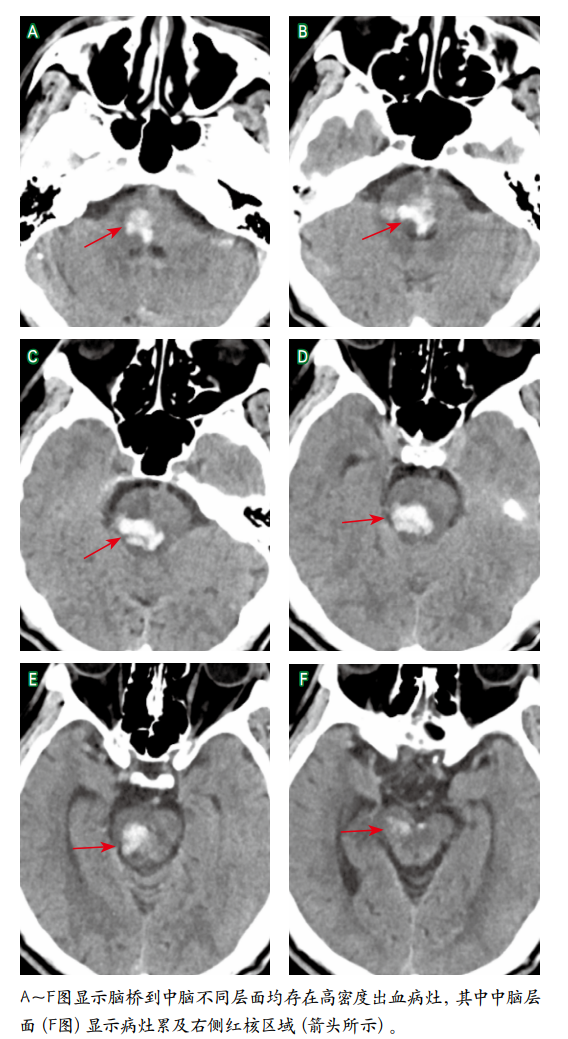

图1 头颅

Figure 1 Results of brain CT examination